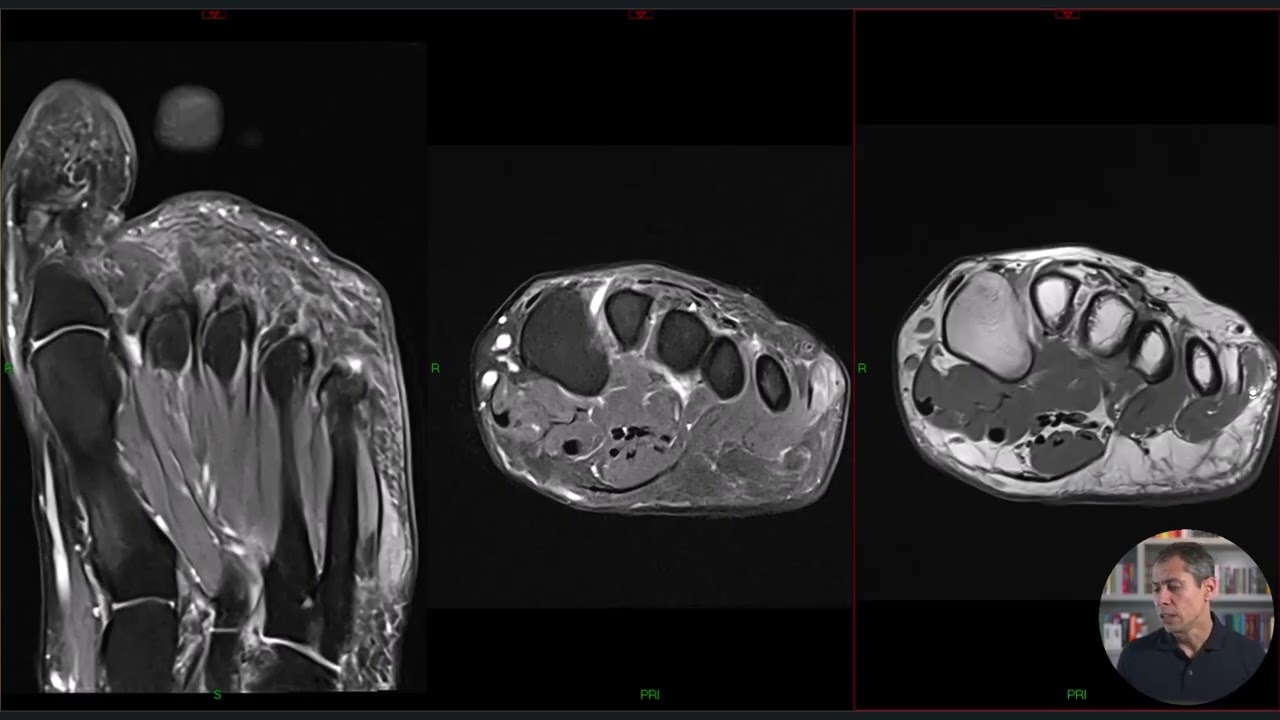

RM na Neuropatia de Baxter (achados no antepé)

Neste vídeo eu gostaria de mostrar os achados de imagem da neuropatia de Baxter na RM do antepé.